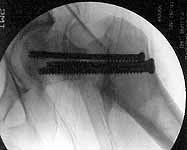

30 y/o man in head-on MVA 12/22/03 sustaining grade II open left femoral midshaft fracture (treated with appropriate staged debridement and retrograde statically locked IM nail), left lateral split tibial plateau fracture (treated with reduction and percutaneous cannulated screw fixation) and comminuted left femoral neck fracture (treated with open reduction and non-compression screw fixation). All initial treatment at another institution and patient recently came to me for follow-up care (he was travelling out of town when he was injured). He has a large (7cm) defect of lateral half of femoral shaft fracture which I plan to pack with a ton of bone graft next week (open fracture site soft tissues healed nicely without sign of infection).

Some additional information. Initial neck treatment was open through lateral

incision with anterior exposure of the fracture. Op note mentions that intra-op

reduction of neck was suboptimal due to comminution, but makes no mention of

state of capsule and I haven't yet been able to speak directly with the treating

surgeon. Attached are intra-op films of neck and films of shaft (not great,

but show the cortical defect). Any further input is invited and welcome.